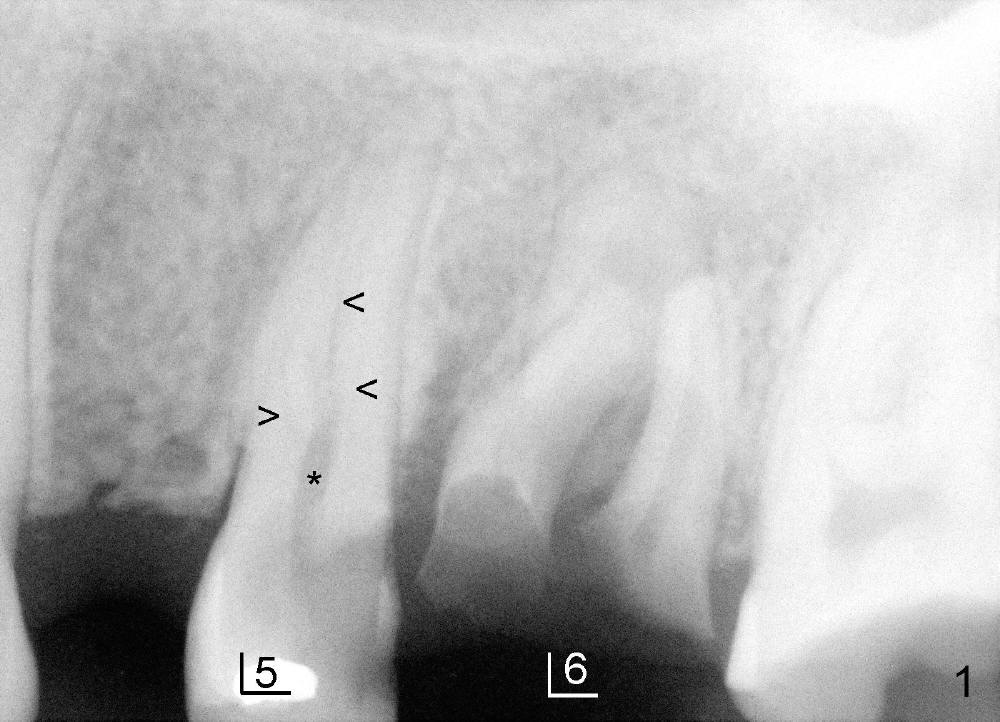

上颌第一前臼齿一般有两个根管(颊侧,鄂侧),偶尔上颌前臼齿有三个根管,可发生于第一或者第二(本例),病人二十四岁,黑人,男,左上第二前臼齿(图一:5)髓腔(*)好像分成三个根管(箭头),仔细观察显示根尖也有三个(图二(图一放大)彩色轮廓与第一磨牙三个根对比:近中颊侧(MB),远中颊侧(DB),鄂侧(P))。因此有三个根管的前臼齿好像小型磨牙,不过颊侧两个根融合。

开髓时发现颊侧(图三B)髓腔比鄂侧(P)宽,根管口分布与上颌磨牙不差上下(图四),图三图四是镜影像。图五显示根管充填后:三个牙胶尖;AH26 Plus 糊剂超填(*),基本在第一磨牙牙槽窝(6)近中,第一磨牙两个月前拔除。根管治疗完成后九天糊剂(图六*)转移到第一磨牙牙槽窝远中,说明牙槽骨象蜂窝,糊剂,细菌自由来往,植牙周围不应该有感染。